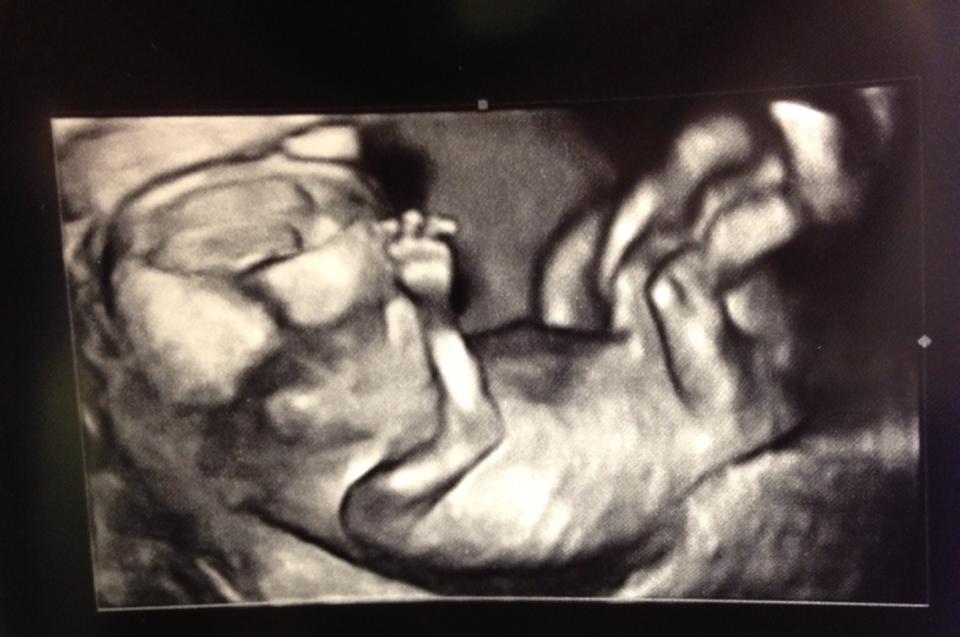

My lil baby :) I think the baby may be a girl HB is 168 and the angle of the dangle lol.image